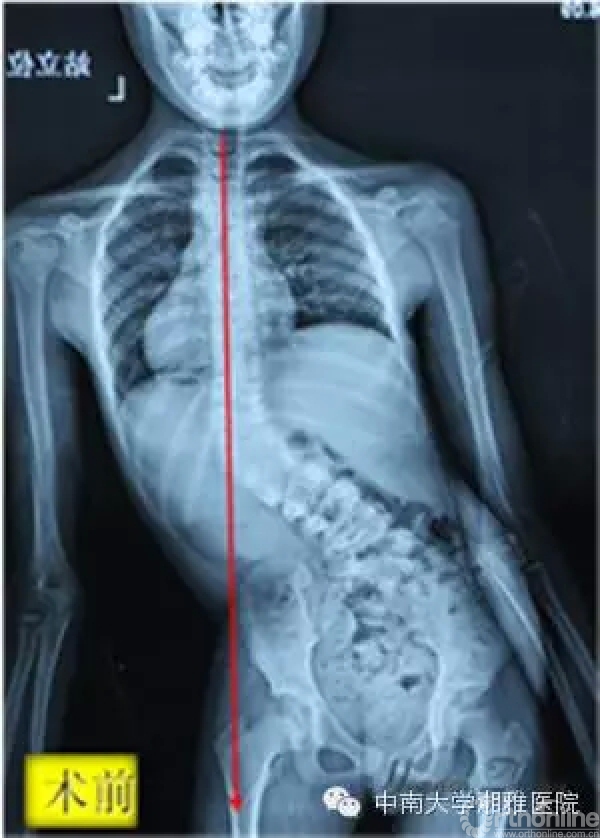

(术前小佳盈的大体照和站立位X片,躯干严重偏斜失衡,需要搀扶才能行走;术后躯干平衡恢复,可自行行走)

初次见到小佳盈,张宏其教授就知道眼前这个9岁的女孩脊柱侧凸畸形十分复杂,如不及时手术中止病情进程,不但现有畸形、外观矫正无从谈起,且不出几年小佳盈势必将全瘫。